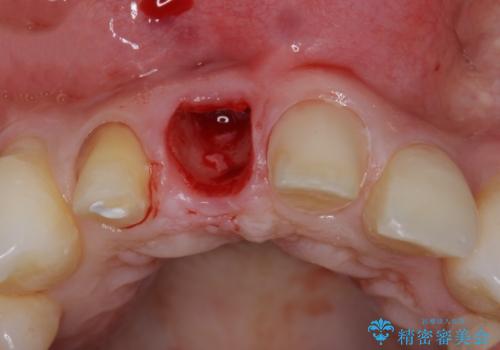

CT撮影を行った結果、右上前歯は吸収が進み抜歯が必要な状態です、

抜歯をせず放置すると、より吸収が進み臨在する歯にも悪影響を及ぼしてしまう可能性が考えられます。